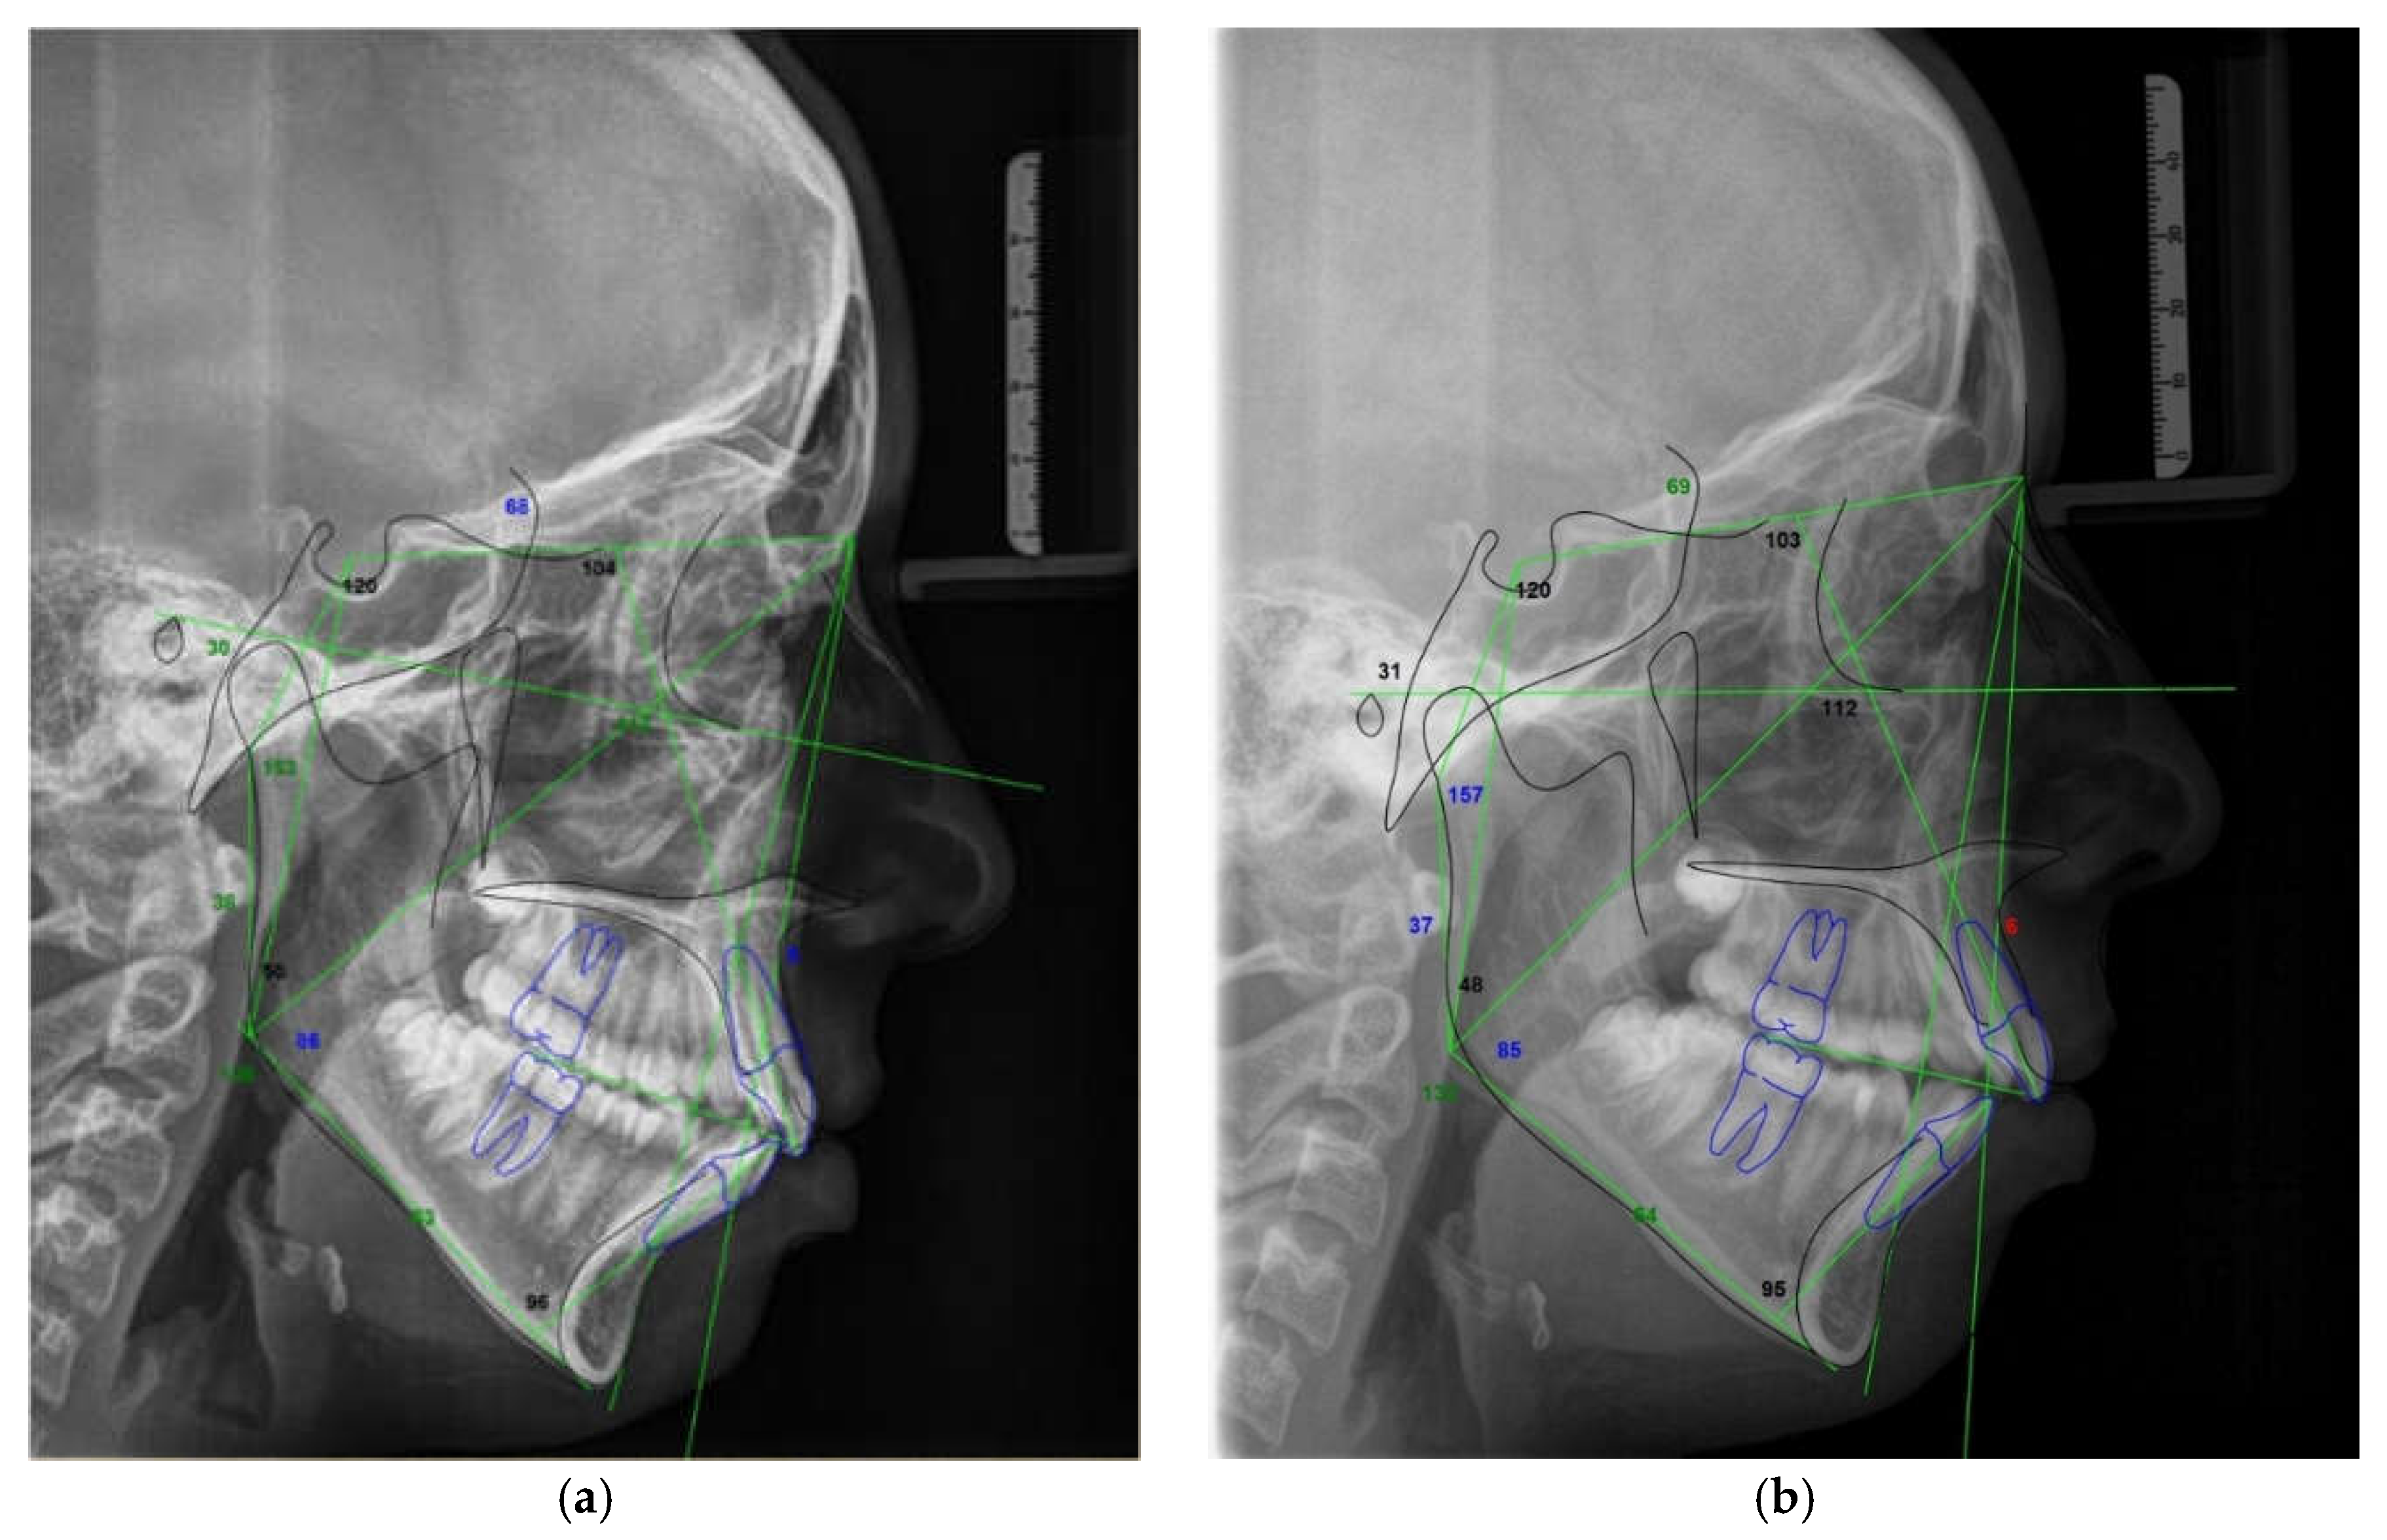

The significant reduction in condylar displacement and the achievement of an orthopedically stable musculoskeletal position following the splint therapy directly correlated with the improvement in TMD symptomatology. Hence, the pain related to the area of the temporomandibular joint and masticatory muscles reported by 55% of patients before the splint therapy was completely eliminated after the splint therapy, and this result was the same for the intermittent jaw locking. Following the splint therapy, headache symptoms were reduced for more than 90% of patients, corresponding with the study findings of Kemper and Okeson [44]. After the splint therapy, jaw clicking was reduced for more than 80% of patients. Clinical findings regarding the signs of tenderness on palpation in the masticatory muscles, lateral pole, temporalis tendon, and posterior attachment inside the ear showed a statistically significant reduction in signs after the splint therapy. Crawford reported a significant increase in the signs and symptoms of TMD as the condylar displacement in vertical and horizontal planes was raised from 1 to 2 mm [12]. He et al. demonstrated that 72.9% of pre-treated orthodontic patients with signs and symptoms of TMD had a condylar displacement greater than 1 mm in the vertical and horizontal and 0.5 mm in the transverse plane, while only 11.4% of asymptomatic patients in the control group had increased condylar displacement. They then concluded that the condylar displacements identified in symptomatic patients were a significant contributory factor to the development of signs and symptoms of TMD [15]. This study found that the significant reduction in condylar displacement obtained via the splint therapy directly correlated with the improvement or elimination of signs and symptoms of TMD, concurring with the findings of similar investigations [7,12,22,23,24,29]. Moreover, our results agreed with those of authors who found a positive correlation between therapy with an occlusal splint constructed in the CR position and improvement in TMD symptomatology, albeit that in these investigations, CPI evaluation was not used [45,46,47,48,49]. Furthermore, a significant increase in condylar displacement between the CR and MI generates changes in the dental relationship that can be observed intraorally in the CR position and from dental casts mounted in the CR. Changes in dental interarch characteristics that occur following deprogramming of the neuromuscular system are presented in Figure 7 and Figure 8.

Figure 7. Intraoral view of occlusion in the MI before splint therapy: (a) Right lateral view; (b) Inferior overjet view; (c) Left lateral view. Intraoral view of occlusion in the CR following splint therapy: (d) Right lateral view; (e) Inferior overjet view; (f) Left lateral view. The magnitude of horizontal (overjet) interarch discrepancy increased and Class II malocclusion was more pronounced. The magnitude of vertical (overbite) interarch discrepancy decreased and lower facial height increased.